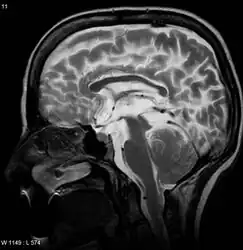

| A sagittal FLAIR MRI scan, from a patient with an Arnold-Chiari malformation, demonstrating tonsillar herniation of 7 mm. | |

Diagnosis is made through a combination of patient history, neurological examination, and medical imaging.[14] Magnetic resonance imaging (MRI) is considered the preferred imaging modality for Chiari malformation.[15] The MRI visualizes neural tissue such as the cerebellar tonsils and spinal cord as well as bone and other soft tissues. CT and CT myelography are other options and were used prior to the advent of MRI, unfortunately the resolution of CT based modalities do not characterize syringomyelia and other neural abnormalities as well.

By convention, the cerebellar tonsil position is measured relative to the basion-opisthion line, using sagittal T1 MRI images or sagittal CT images.[16] The selected cutoff distance for abnormal tonsil position is somewhat arbitrary, as not every person will be symptomatic at a certain amount of tonsil displacement, and the probability of symptoms and syrinx increases with greater displacement; however, greater than 5 mm is the most frequently cited cutoff number, though some consider 3–5 mm to be "borderline,"; pathological signs and syrinx may occur beyond that distance.[16][17][18] One study showed little difference in cerebellar tonsil position between standard recumbent MRI and upright MRI for patients without a history of whiplash injury.[13] Neuroradiological investigation is used to first rule out any intracranial condition that could be responsible for tonsillar herniation. Neuroradiological diagnostics evaluate the severity of crowding of the neural structures within the posterior cranial fossa and their pressure against the foramen magnum. Chiari 1.5 is a term used when both brainstem and tonsillar herniation through the foramen magnum are present.[19]